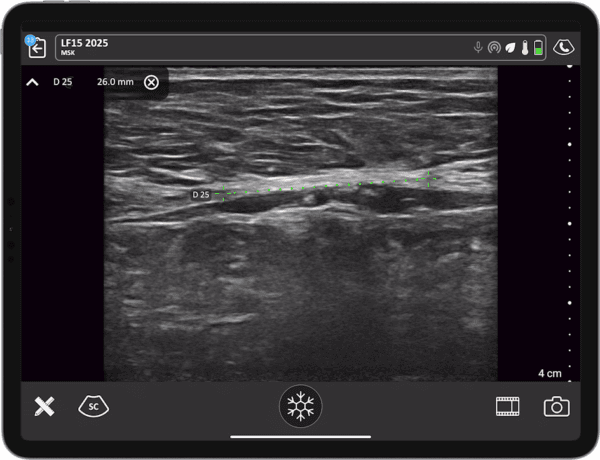

Point-of-care ultrasound can be a valuable tool in the diagnosis and management of diastasis recti. With real-time imaging, surgeons can elevate planning, execution, and postoperative care to ensure optimal aesthetic and functional outcomes.

- How diastasis recti is diagnosed using wireless ultrasound

- How to tailor surgical approaches based on ultrasound findings, including assessment of rectus muscle thickness and integrity

Dr. Khanh Nguyen will present a real pre-operative assessment, surgical case series, and examples of post-operative complications, highlighting the benefits of using wireless ultrasound for his patient assessments.